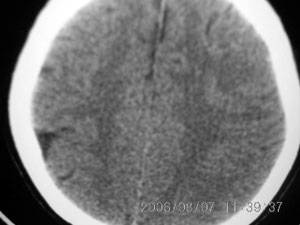

标题: CT4285:头部病变,女 21岁

女 21岁 发作性面色发白一年,每次发作仅数秒钟

局部软化灶,脑沟增宽加深,考虑为脑血管畸形可能,建议增强或mri检查.

左颞顶叶不规则低迷度影边界尚清楚,岁数年轻,应考虑脑血管畸形。建议强化或核磁,进一步检查。

局限性脑软化灶,右侧侧脑室后角受吸引,略有拉伸。考虑动静脉畸形。